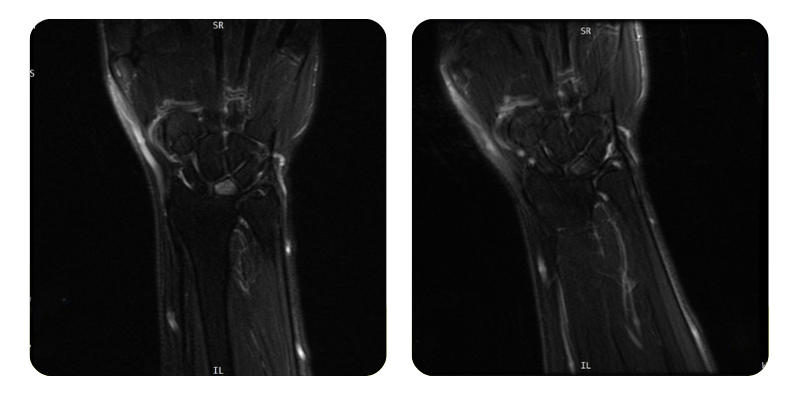

Before

After

B.A.A., 54 years old - Avascular osteonecrosis of the left lunate

Anamnesis: The patient presents with avascular osteonecrosis of the left lunate; works as a pastry chef; no history of trauma.

Results: Hand MRI.

Evolution: After completing 20 hyperbaric therapy sessions, the patient shows an improvement of approximately 80%, with complete disappearance of pain in the left hand. No functional limitations are observed, and the patient has resumed her normal activities without discomfort.